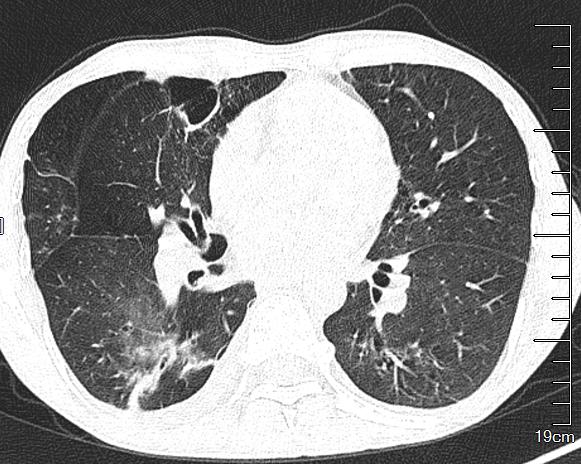

健康肺部ct图片 正常

健康肺部ct图片 正常,正常肺部ct图解